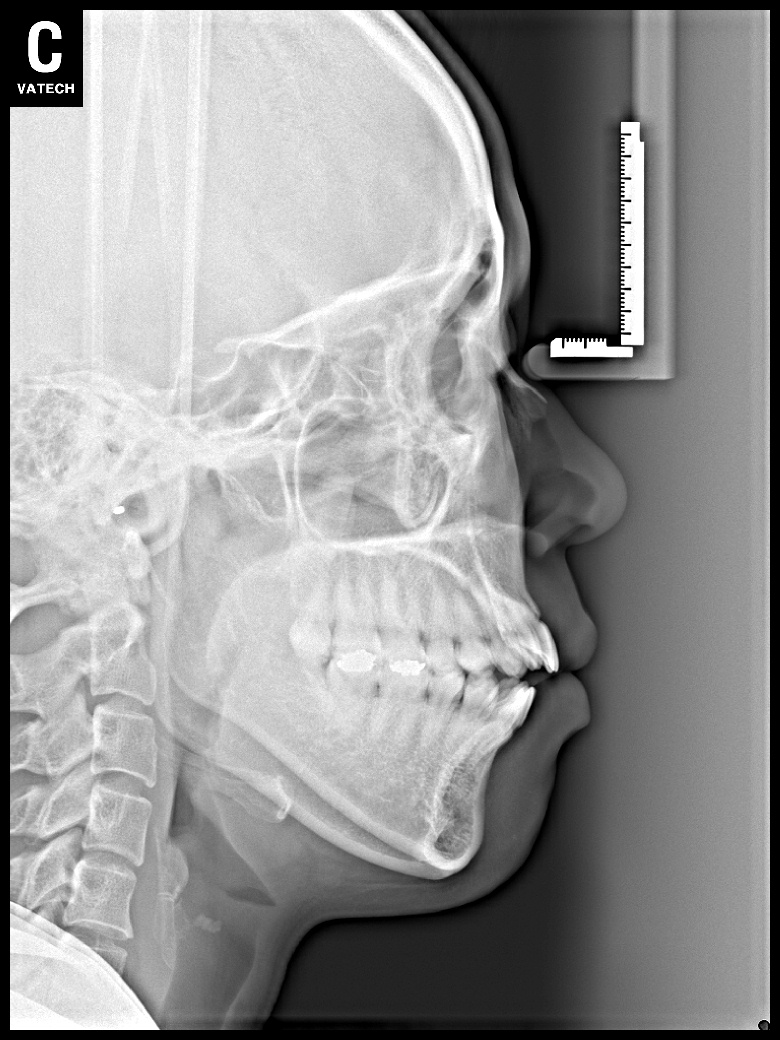

치료 후 사진입니다.